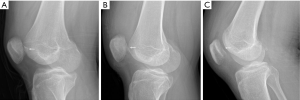

Each patient had two-viewed X-ray (Figure 2A), CT, and MR exams preoperatively. MRI showed lateral femoral condylar bone marrow edema and MPFL lesions (Figure 2B). Computer tomography reconstruction images were also available for further diagnosis of the OCFs (Figure 2C,D). All 18 patients underwent X-ray (Figure 3) and MRI examinations postoperatively. Postoperative MRI showed the fixation fracture fragments and the image of drill channels (Figure 4). All of them showed good healing of the OCFs. However, the MRI showed that 4 patients had anterior patellar bursa with no clinical symptoms. There were small areas of cartilage thinning but no obvious sign of joint degeneration.